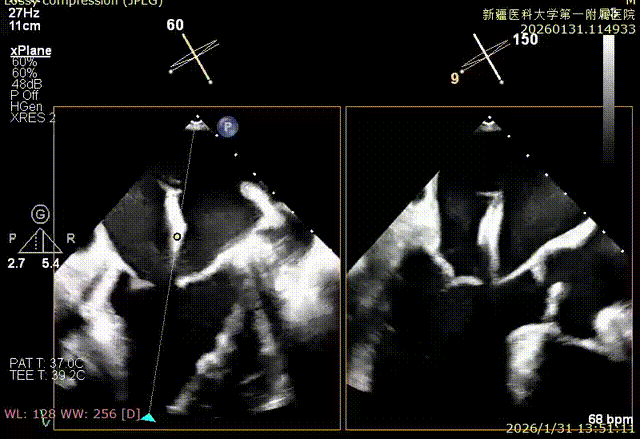

SGC进入左房

XTR初定位

XTR弹道测试

3D enface 完成Orientation调整